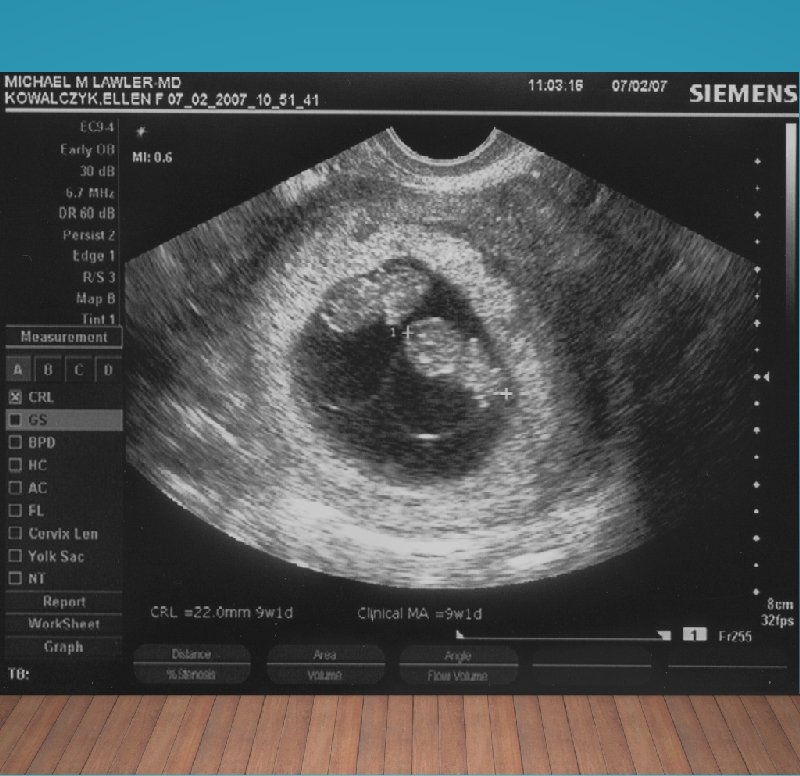

Ultrasounds